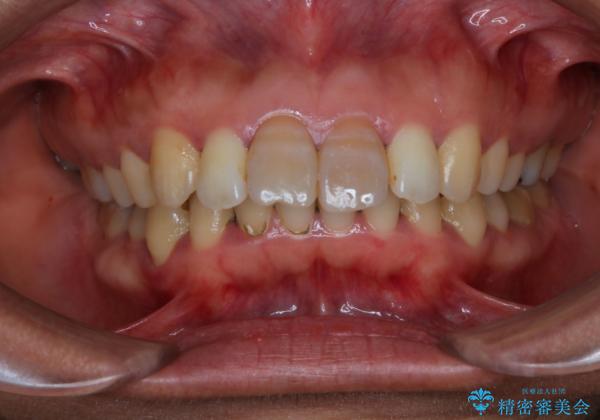

- 前歯の色が気になるとのことでご相談にいらした患者様です。診断の結果、前歯は2本とも失活していたために精密根管治療から治療を開始しました。根管治療後にウォーキングブリーチを行うことで歯の色をトーンアップさせました。患者様より周囲の歯も全体的に白くしたいとのご希望があったため、オフィスホワイトニングも併せて行いました。

ウォーキングブリーチ法とは歯の中に薬剤を入れて内側からホワイトニングを行う方法であるため、根管治療がされている歯のみ適応となります。生活歯(神経が生きている歯)に対してはオフィスホワイトニングやホームホワイトニングが有効です。